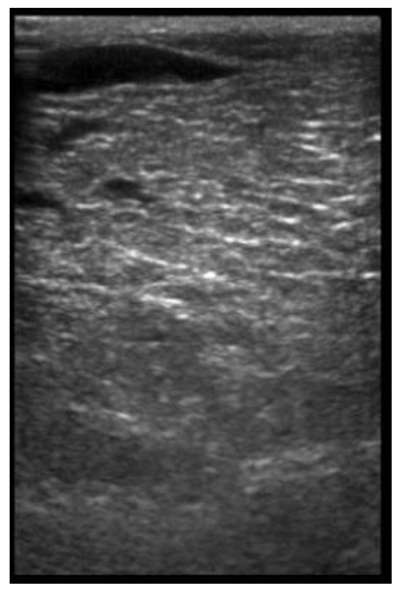

| 113 days of pregnancy (P113) Scanning depth 4.7 cm | ![]() | ![]() | MT generous: 28.9 mm MT conservative: 25.9 mm Gland cistern: 3.3 mm Parenchyma: 10.9 mm Fat Pad: 10.0 mm |

| 109 days of pregnancy (P109) Scanning depth 4.7 cm | ![]() | ![]() | MT generous: 36.8 mm MT conservative: 27.2 mm Gland cistern: 4.7 mm Parenchyma: 15.4 mm Fat Pad: 5.5 mm |

| 107 days of pregnancy (P107) Scanning depth 4.7 cm | ![]() | ![]() | MT generous: 31.7 mm MT conservative: 22.3 mm Gland cistern: 4.5 mm Parenchyma: 8.3 mm Fat Pad: 7.8 mm |

| 107 days of pregnancy (P107) Scanning depth 4.7 cm | ![]() | ![]() | MT generous: 32.2 mm MT conservative: 25.3 mm Gland cistern: 3.6 mm Parenchyma: 12.4 mm Fat Pad: 7.9 mm |